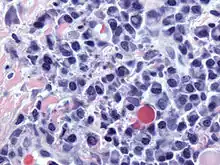

Russell bodies

Russell bodies are inclusion bodies usually found in atypical plasma cells that become known as Mott cells.[1] Russell bodies are eosinophilic, homogeneous immunoglobulin (Ig)-containing inclusions usually found in cells undergoing excessive synthesis of Ig; the Russell body is characteristic of the distended endoplasmic reticulum. Russell bodies are large and globular of varying size, and become packed into the cell's cytoplasm pushing the nucleus to the edge of the cell, and are found in the peripheral areas of tumors. Russell bodies are thought to have originated as abnormal proteins that have not been secreted. The excess immunoglobulin builds up and forms intracytoplasmic globules, which is thought to be a result of insufficient protein transport within the cell. This causes the proteins to neither be degraded or secreted and stay stored in dilated cisternae.[2] In 1949, Pearse discovered that Russell bodies also contain mucoproteins that are secreted by plasma cells. Russell bodies are not tissue specific; during research they were induced in rat glioma cells.[3] Russell bodies were found to have positive reactions to PAS stain, CD 38 and CD 138 stains. Plasma cells that contain Russell bodies and are stained with H&E stain are found to be autofluorescent, while those without Russell bodies are not. Russell bodies tend to be found in places with chronic inflammation.

This is one cell variation found in multiple myeloma.[4]